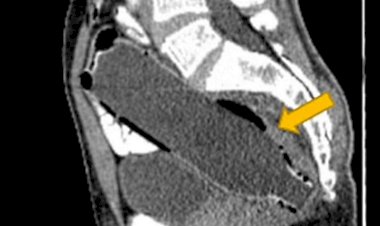

O presidente eleito Luiz Inácio Lula da Silva deu entrada ontem (20), no Hospital Sírio-Libanês, em São Paulo, para a realização de uma laringoscopia para retirada de leucoplasia da prega vocal esquerda, uma lesão na laringe.